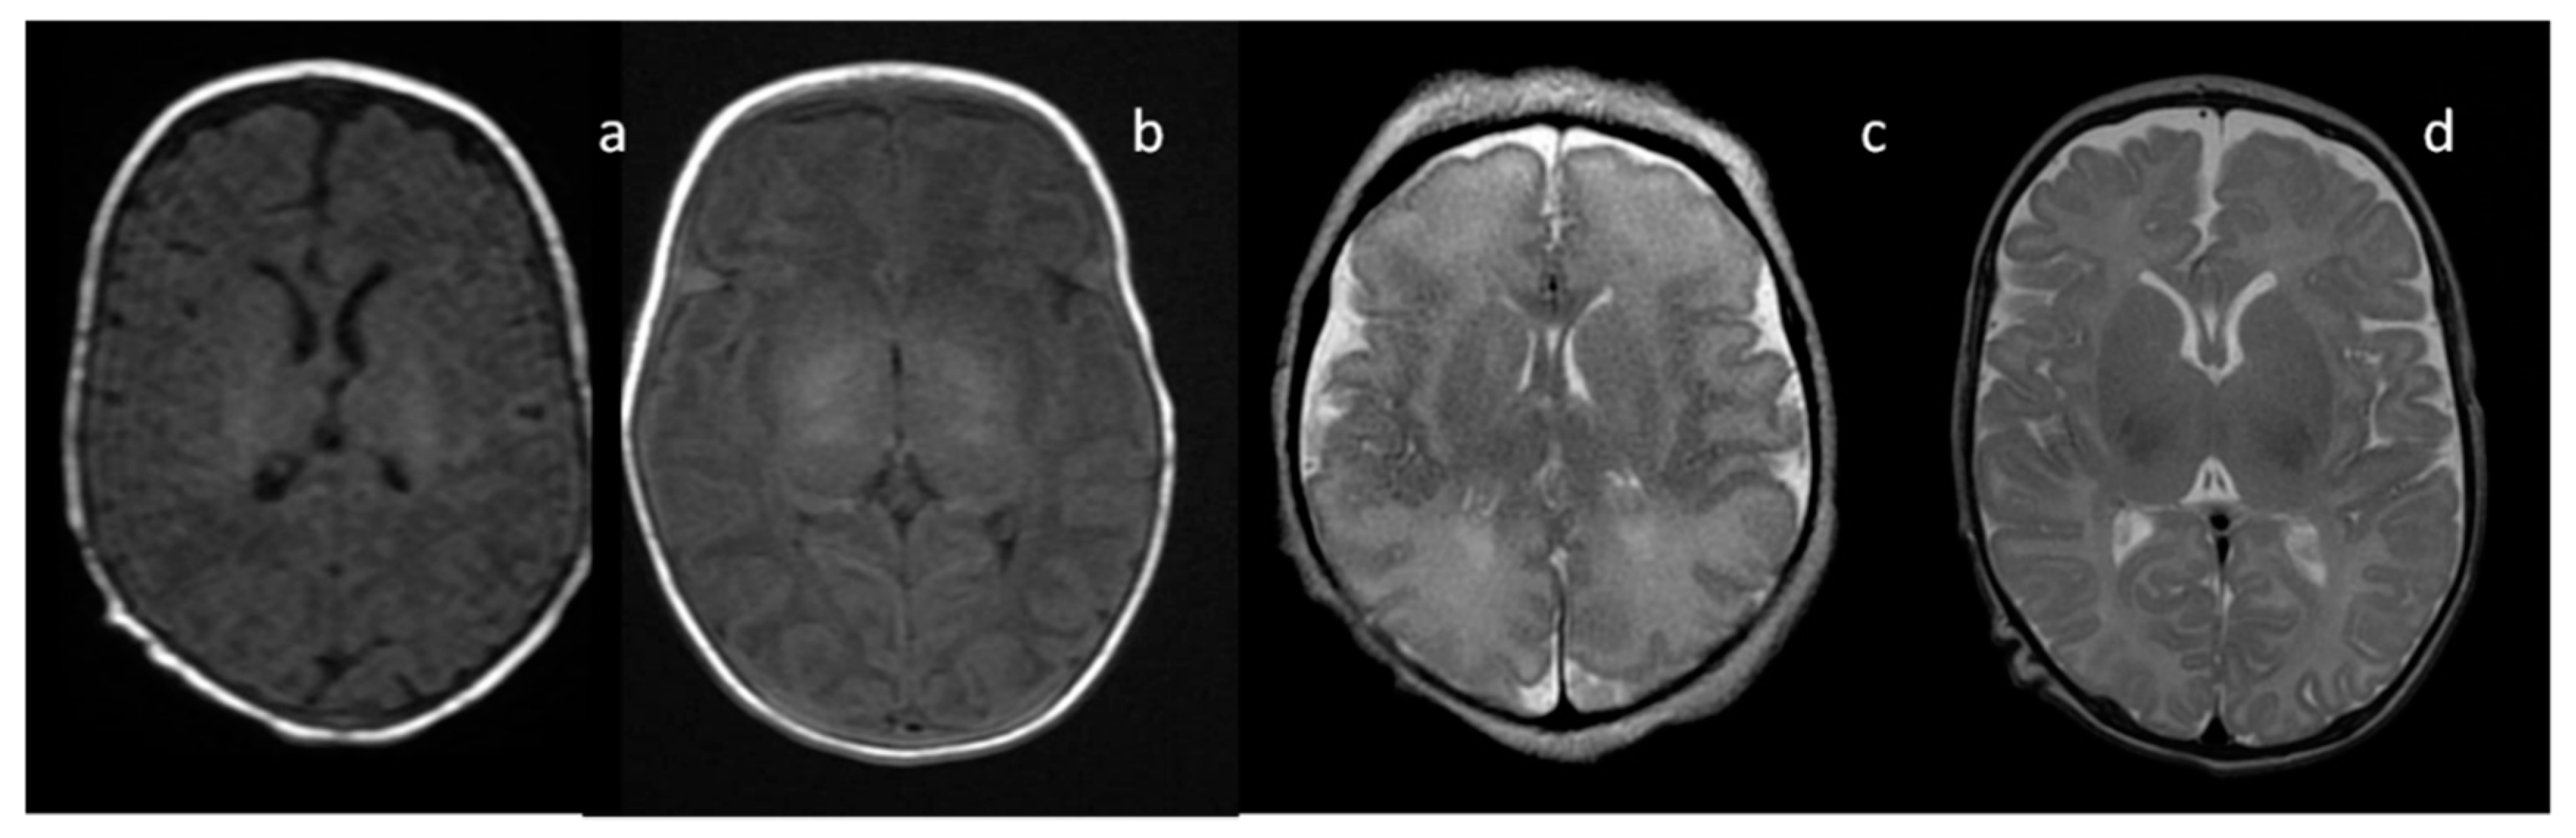

4.1. Mitochondrial Disorders

4.2. Neurodegeneration with Brain Iron Accumulation (NBIA)

4.3. Biotin-Thiamine-Responsive Basal Ganglia Disease (BTBGD)

4.4. Pyruvate Dehydrogenase Deficiency (PDHD)

4.5. Glutaric Aciduria (GA) Type 1

4.6. Gangliosidosis (GM1 and GM2)